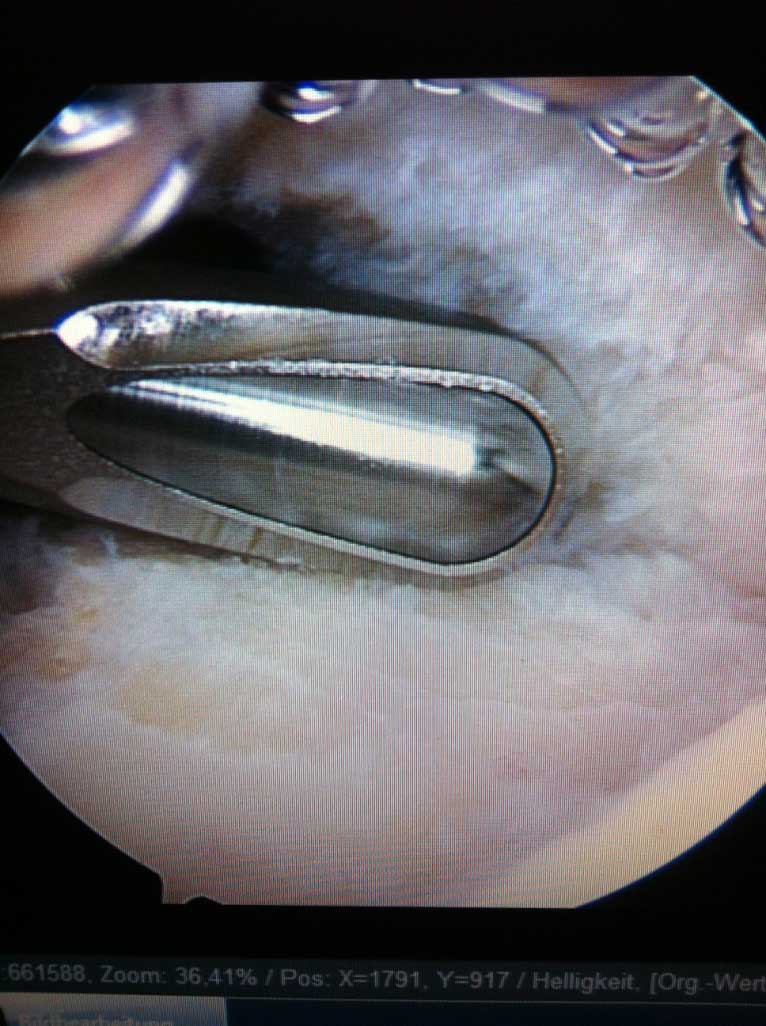

Wird die Indikation zur Sehnennaht / Rekonstruktion der gerissenen Sehnen gestellt, so wird die Operation in unseren Händen ausschließlich arthroskopisch (Schlüsselloch Operation) durch 3 - 6 kleinen Stichinzisionen (3-4mm) durchgeführt. Dieses operative Verfahren ist maximal zu den schulterumgebenden  Weichteilen schonend.

Je nach Alter, Verletzungsmuster, Anzahl der Luxationsereingnisse und weiteren Faktoren, wird eine schulterstabilisierende Operation indiziert und empfohlen. Diese führen wir ebenfalls ausschliesslich arthroskopisch

(Schüsselloch Operation) durch. Innerhalb von 15 - 30 min wird dabei der knorpelige Ring (s.g. Labrum) auf den knöchernen Pfannenrand mit speziellen Anker und Fäden wieder zurück befestigt.